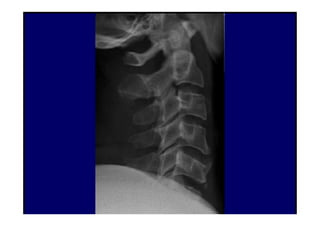

Anatomia Radiológica Cervical

1. Radiografia Simples

Radiografia da coluna cervical

Série de Radiografias Simples

da Coluna Cervical

• 1- Incidência AP com a boca aberta (para visualizar C1-C2);

• 2- Incidência AP cervical inferior;

• 3- Incidência cervical lateral (perfil);

• 4- Incidências oblíquas direita e esquerda;

• 5- Incidências adicionais:

- Incidência lateral em flexão e extensão

- Incidência de Fuch

- Incidência dos pilares de Boyleston

07/12/2015 Dr. José Heitor M. Fernandes 65

AP Lateral